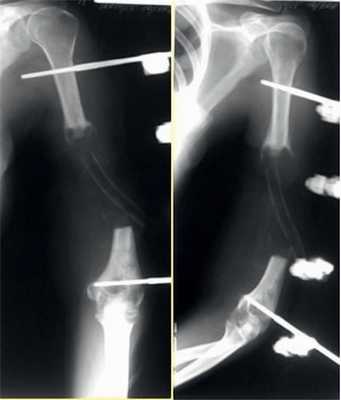

Переломы диафиза плечевой кости у детей встречаются нечасто. Клиническая картина типична. Переломы в средней трети плечевой кости опасны вследствие возможного повреждения лучевого нерва, который на этом уровне огибает плечевую кость. Смещение отломков может вызвать травматический парез или, в тяжелых случаях, нарушение целости нерва. В связи с этим все манипуляции при переломе в средней трети диафиза плечевой кости необходимо производить с особой осторожностью. Применяют метод одномоментной закрытой репозиции с последующей фиксацией в гипсовой лонгете или метод скелетного вытяжения за проксимальный метафиз локтевой кости, что дает лучший результат. Если при последующем рентгенологическом контроле обнаруживают вторичное смещение отломков, то его устраняют наложением корригирующих тяг. Обращают внимание на правильность оси плечевой кости, ибо смещение костных отломков по длине до 2 см хорошо компенсируется, в то время как угловые деформации в процессе роста не устраняются.

При значительных отеках, неудаче одномоментной закрытой репозиции целесообразно применить метод скелетного вытяжения за проксимальный метафиз локтевой кости с грузом от 2 до 3 кг. Если перелом нестабильный (чаще наблюдается при косой плоскости), можно воспользоваться чрескожной фиксацией костных отломков по К. Паппу (диафиксация) или чрескожным остеосинтезом перекрещенными спицами Киршнера по методике Джуде. При неудаче консервативного лечения и недопустимом смещении отломков может возникнуть необходимость в открытой репозиции. Операцию производят в крайних случаях: при повторных безуспешных попытках закрытой репозиции, при интерпозиции сосудисто-нервного пучка между отломками с угрозой образования ишемической контрактуры Фолькманна, при открытых и неправильно срастающихся переломах.